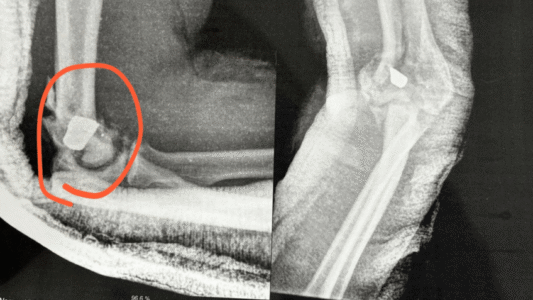

O cantor gospel João Igor, que foi baleado por um policial militar, na quarta-feira (30), no Terminal da Barra Funda, na capital paulista, está com o projétil alojado no braço e deverá passar por uma cirurgia de risco, segundo informou a advogada Aline Sousa, que o representa.

À CNN, a defensora do cantor gospel enviou o resultado de um raio-x feito pelo homem, que mostra os projétil e alguns estilhaços dentro do braço de João.

Imagem mostra raio-x de cantor baleado por PM na Rodoviária da Barra Funda • Reprodução

A advogada informou que, de acordo com o ortopedista, devido a alta presença dos estilhaços da munição no local atingido, a cirurgia do cantor é colocada em risco.